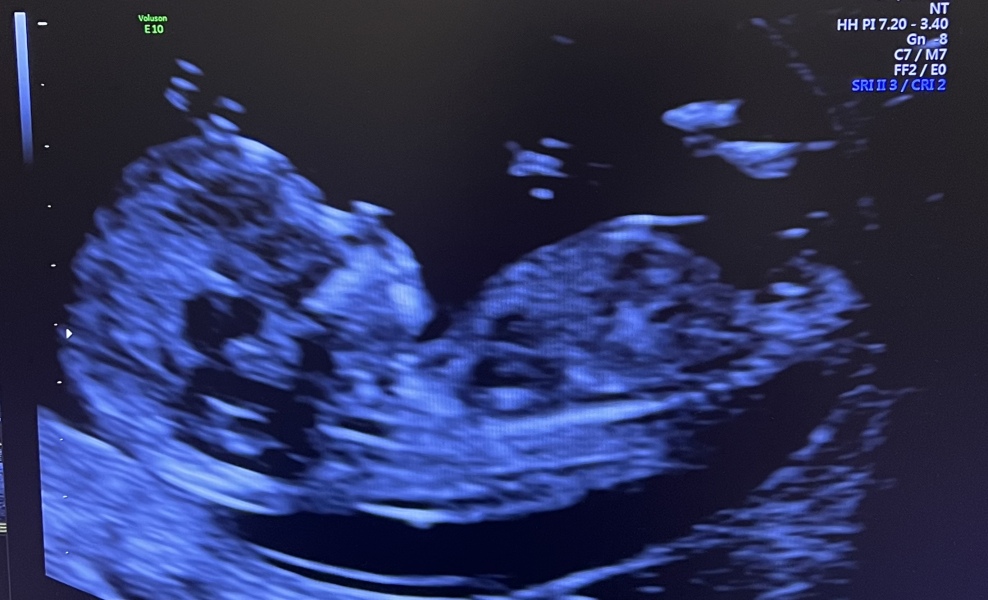

@allgoodthings84 yes all went well 🤍🤍🤍✨ got a lovely pic too 🤍🤍 what date in Aug are you due?

yes I had my 12 (13) week scan ✨🤍 all results are good so far, baby looked happy and healthy in the scan.

@NSx that’s a lovely scan picture 💕